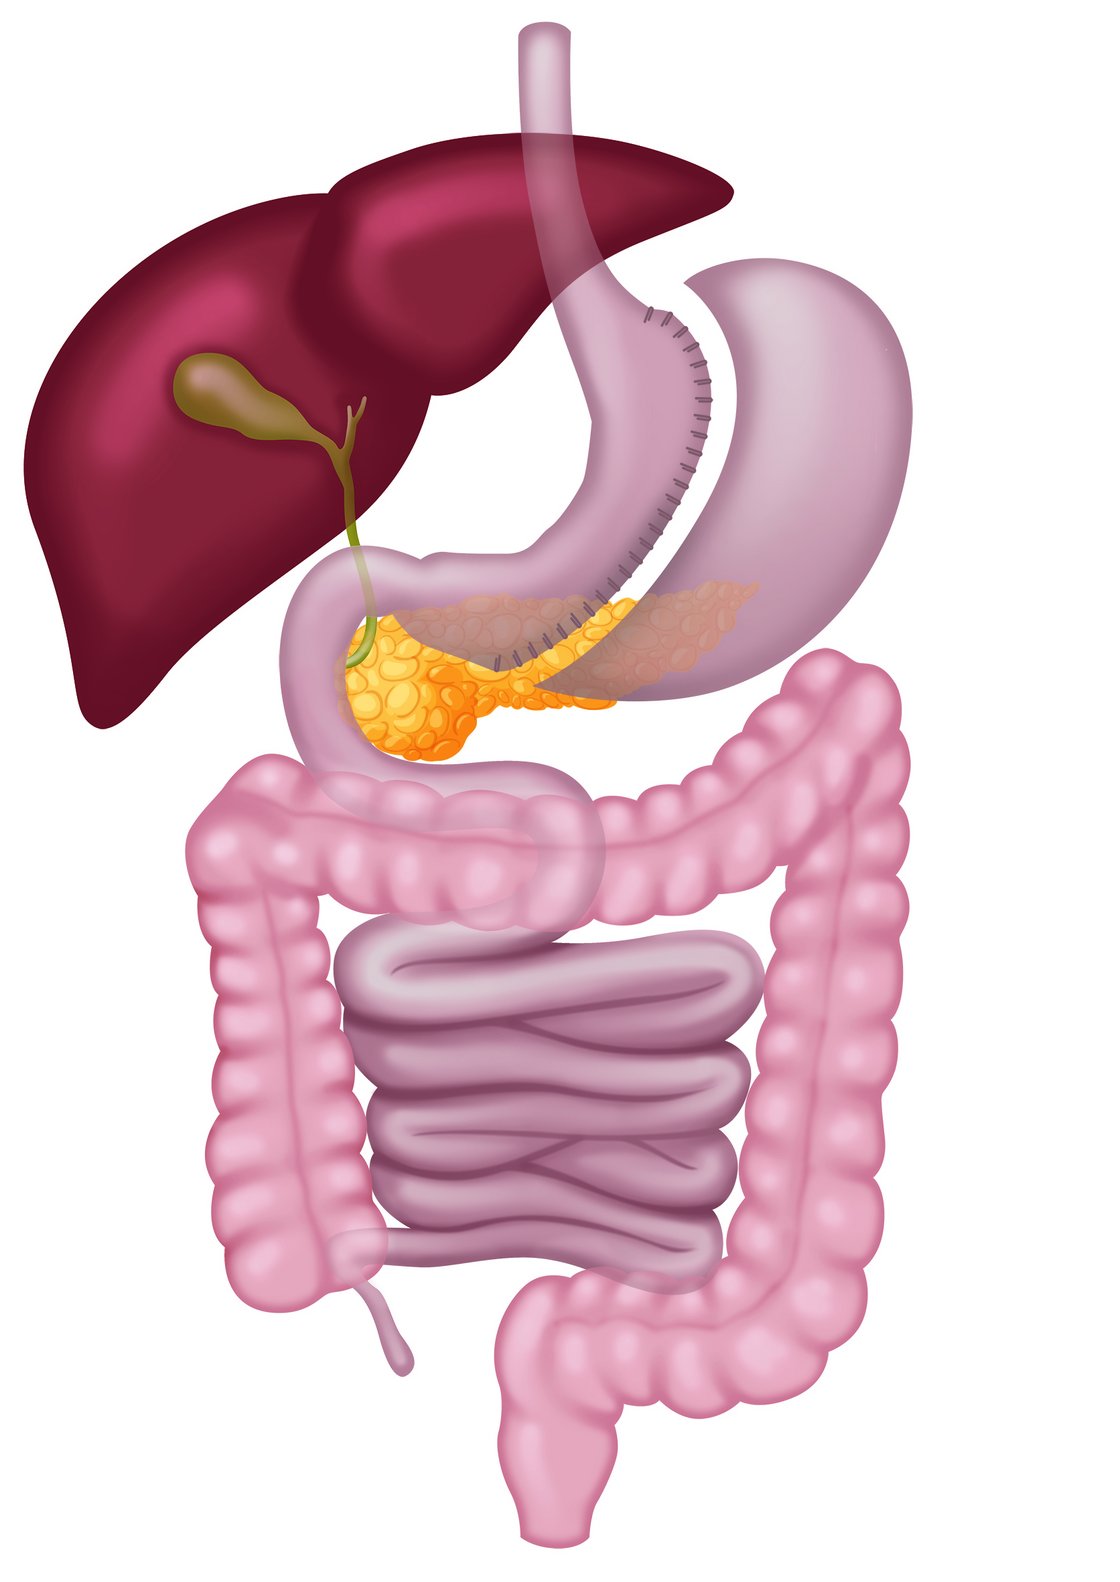

- hoher BMI (>50 kg/m²)

- Verkleinerung des Magens (finale Lösung nicht reversibel)

- zusätzliche Vitamin- und Spurenelementaufnahme notwendig

- Umwandlung zum Magenbypass oder weitere Operationsmethoden möglich